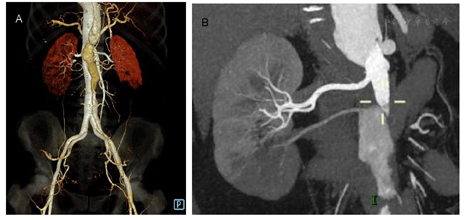

腹腔干起始部呈鱼钩状改变,管腔狭窄;腹腔干、肠系膜上动脉骑跨于真假腔,腹腔干假腔供血为主,肠系膜上动脉真腔供血略占优势,二者管腔充盈良好。双肾动脉起自真腔,右侧副肾动脉起自假腔,其供血区灌注明显减低(图2A~B);肠系膜下动脉起自假腔,充盈尚可。